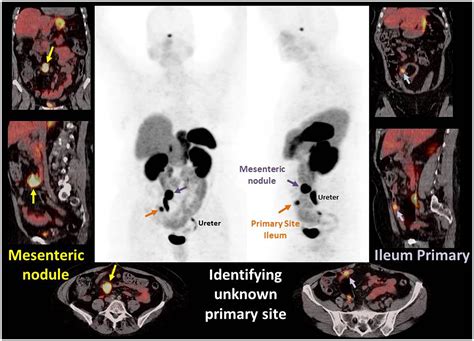

The "Dotatate" component is a radioactive pharmaceutical agent. It acts as a targeted seeking device that binds to somatostatin receptors. These receptors are often found in high concentrations on the surface of neuroendocrine tumor cells. Because these tumors "light up" when the tracer binds to them, the PET scan creates a vivid map of where these tumors are located throughout the body, even those that are too small to be detected by standard imaging.

Your healthcare provider might recommend a Dotatate PET scan for several critical reasons related to the management of neuroendocrine tumors. Its primary function is to provide a comprehensive look at the extent of the disease.

• Accurate Staging: It helps doctors determine how far a tumor has spread (metastasized) from its original site.

• Treatment Planning: By identifying precisely where the tumors are, surgeons or oncologists can better decide on the most effective course of treatment, such as surgery, radiation, or specialized medical therapies like peptide receptor radionuclide therapy (PRRT).

Once the scan is complete, the images are sent to a radiologist or nuclear medicine physician who specializes in interpreting these complex studies. They will analyze the images to identify areas of high tracer uptake, which indicate the presence of neuroendocrine tumor cells. The results are typically combined with findings from other tests and your clinical history to provide a comprehensive summary of your condition.